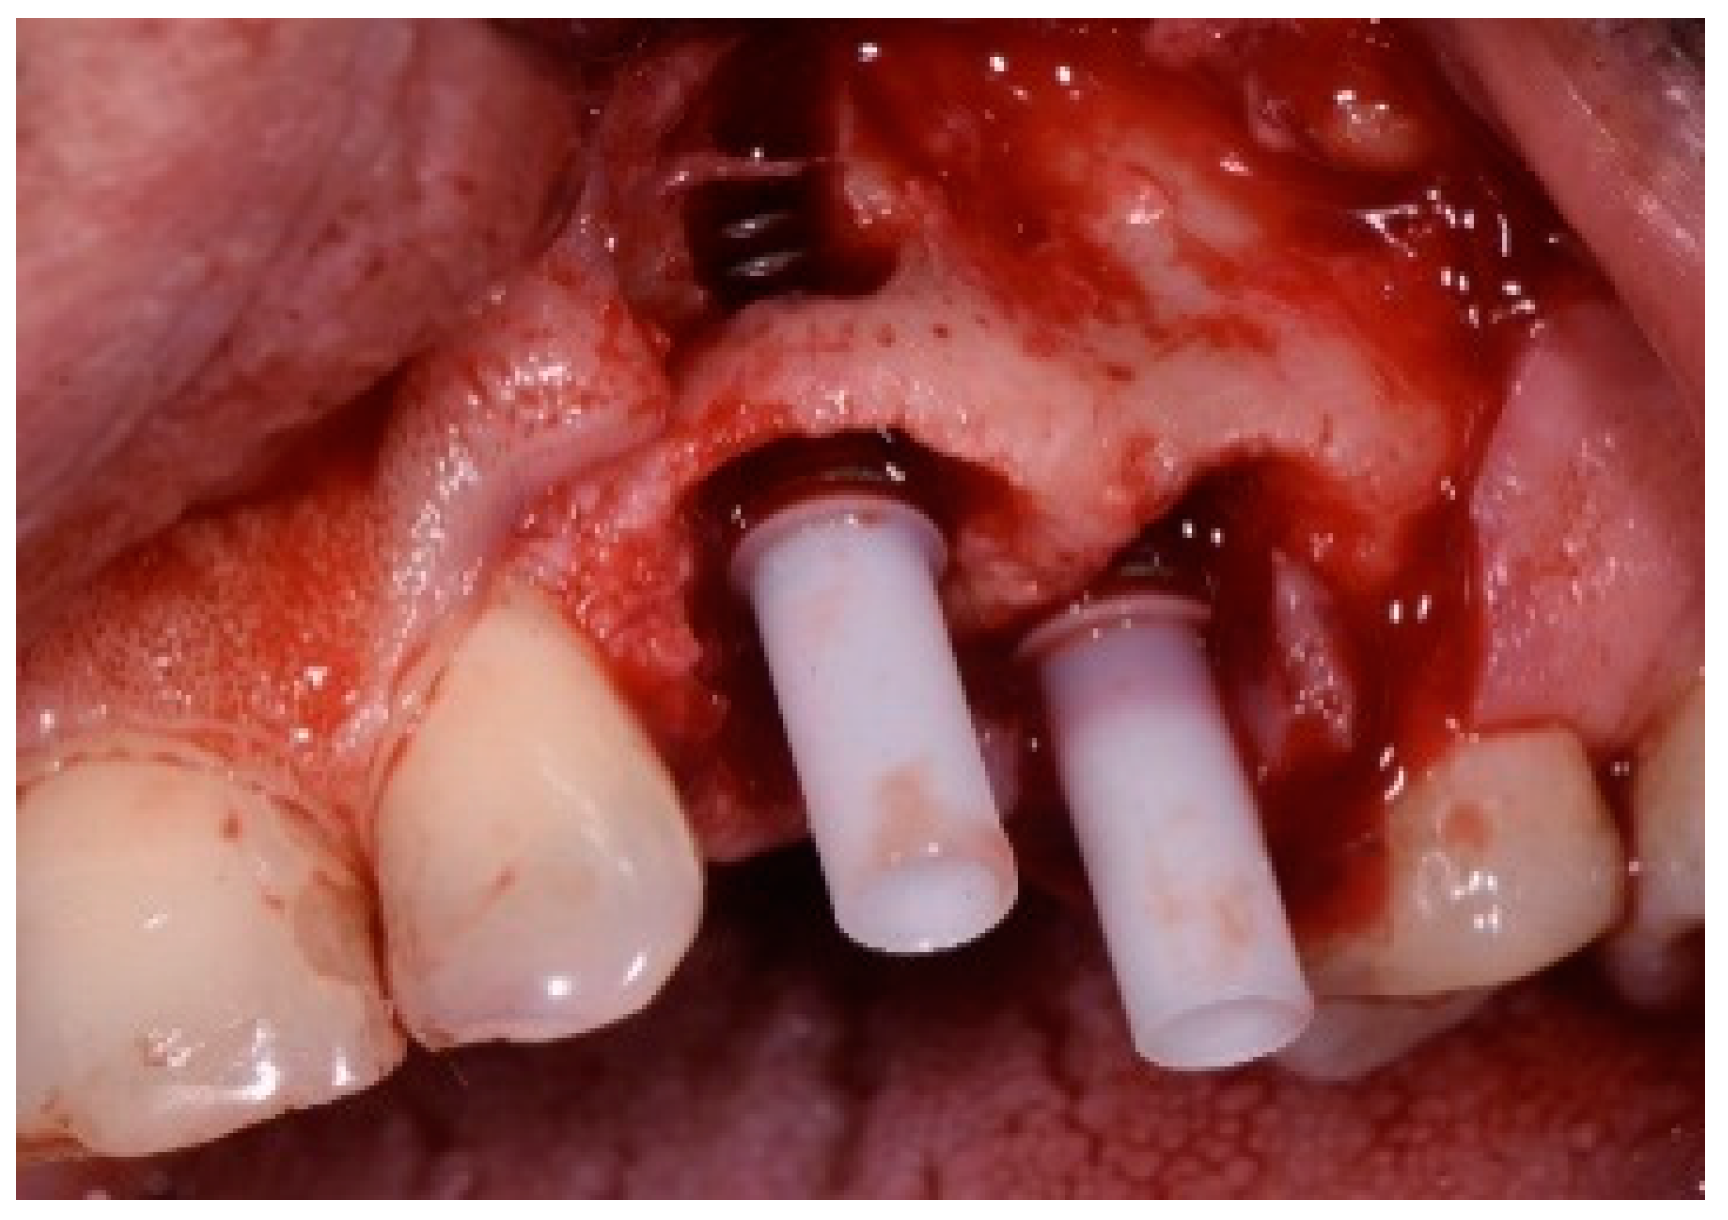

One hour before the surgical procedure, the patient received a prophylactic dose of 1 g of amoxicillin. Following local anesthesia, surgical access was obtained by raising a full-thickness aesthetic flap extending to the distal line angles of the lateral incisors. The full-thickness flap was extended 3–5 mm beyond the apical margin of the defect. The two central incisor roots were extracted, and the sockets were curetted with surgical curettes to remove all the granulation tissue (Figure 2). The sockets were assessed for the presence of a dehiscence and or fenestration. Two implants (Adin Dental Implants, Englewood, NJ, 07632, USA) were placed according to the manufacturer’s instructions (Figure 3).

Figure 2.

Clinical view immediately after extraction.

Figure 3.

Clinical view of the placement of two maxillary anterior implants.